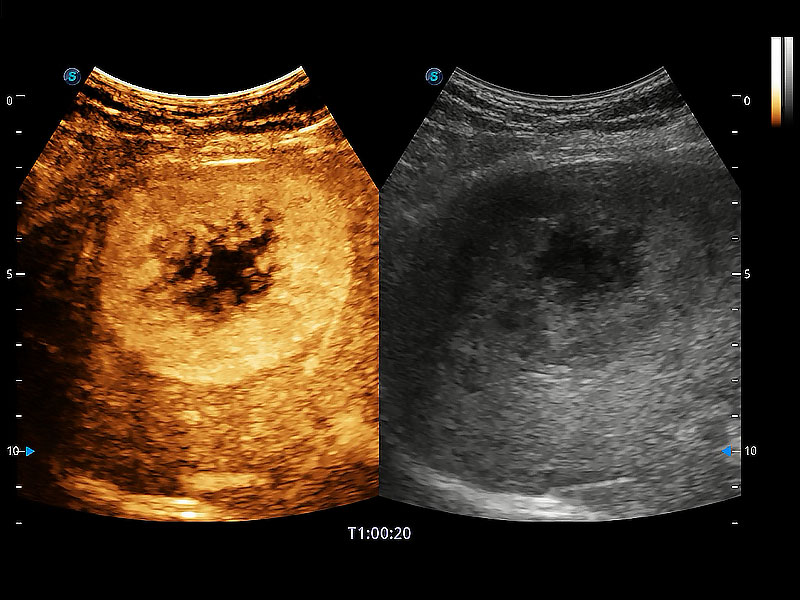

极大提升超低速微细血流的检出能力,同时更精准地滤除软组织和超声信号,为兽用医生提供以往无法通过常规血流获得的疾病诊断信息。

非线性融合造影成像充分利用谐波和基波信号,为难以观察的血流进行增强显像。可用于线阵、凸阵、微凸阵、相控阵探头。